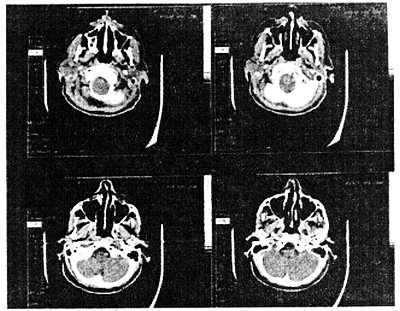

После того как были получены и оцифрованы все изображения, компьютер составляет двумерную модель, которая показывает разрез тела пациента (рис. 10.24).

Рис. 10.24. Изображение головы, полученное с помощью компьютерного аксиального томографа